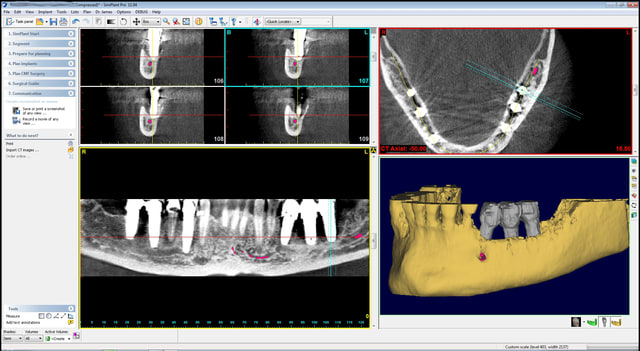

quelques images en 3 D...

Bernard cross section apfhj5 - Eugenol

Bernard cross section  2  ctt7jw - Eugenol

Bernard overview edbft1 - Eugenol

Bernard overview  2  nlgyly - Eugenol

Bernard panoramic l8hei0 - Eugenol